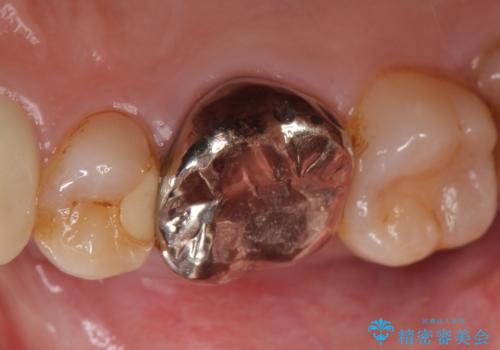

今回用いたオールセラミッククラウンはジルコニアフレームという白い素材の上にセラミックを盛っているため、審美性が非常に高いのが特徴です。

また、ジルコニアは人工ダイヤモンドの材料にも使われているほど高い強度を持っており、そのためオールセラミッククラウンは審美性だけでなく、奥歯やブリッジの補綴も可能とするクラウンです。